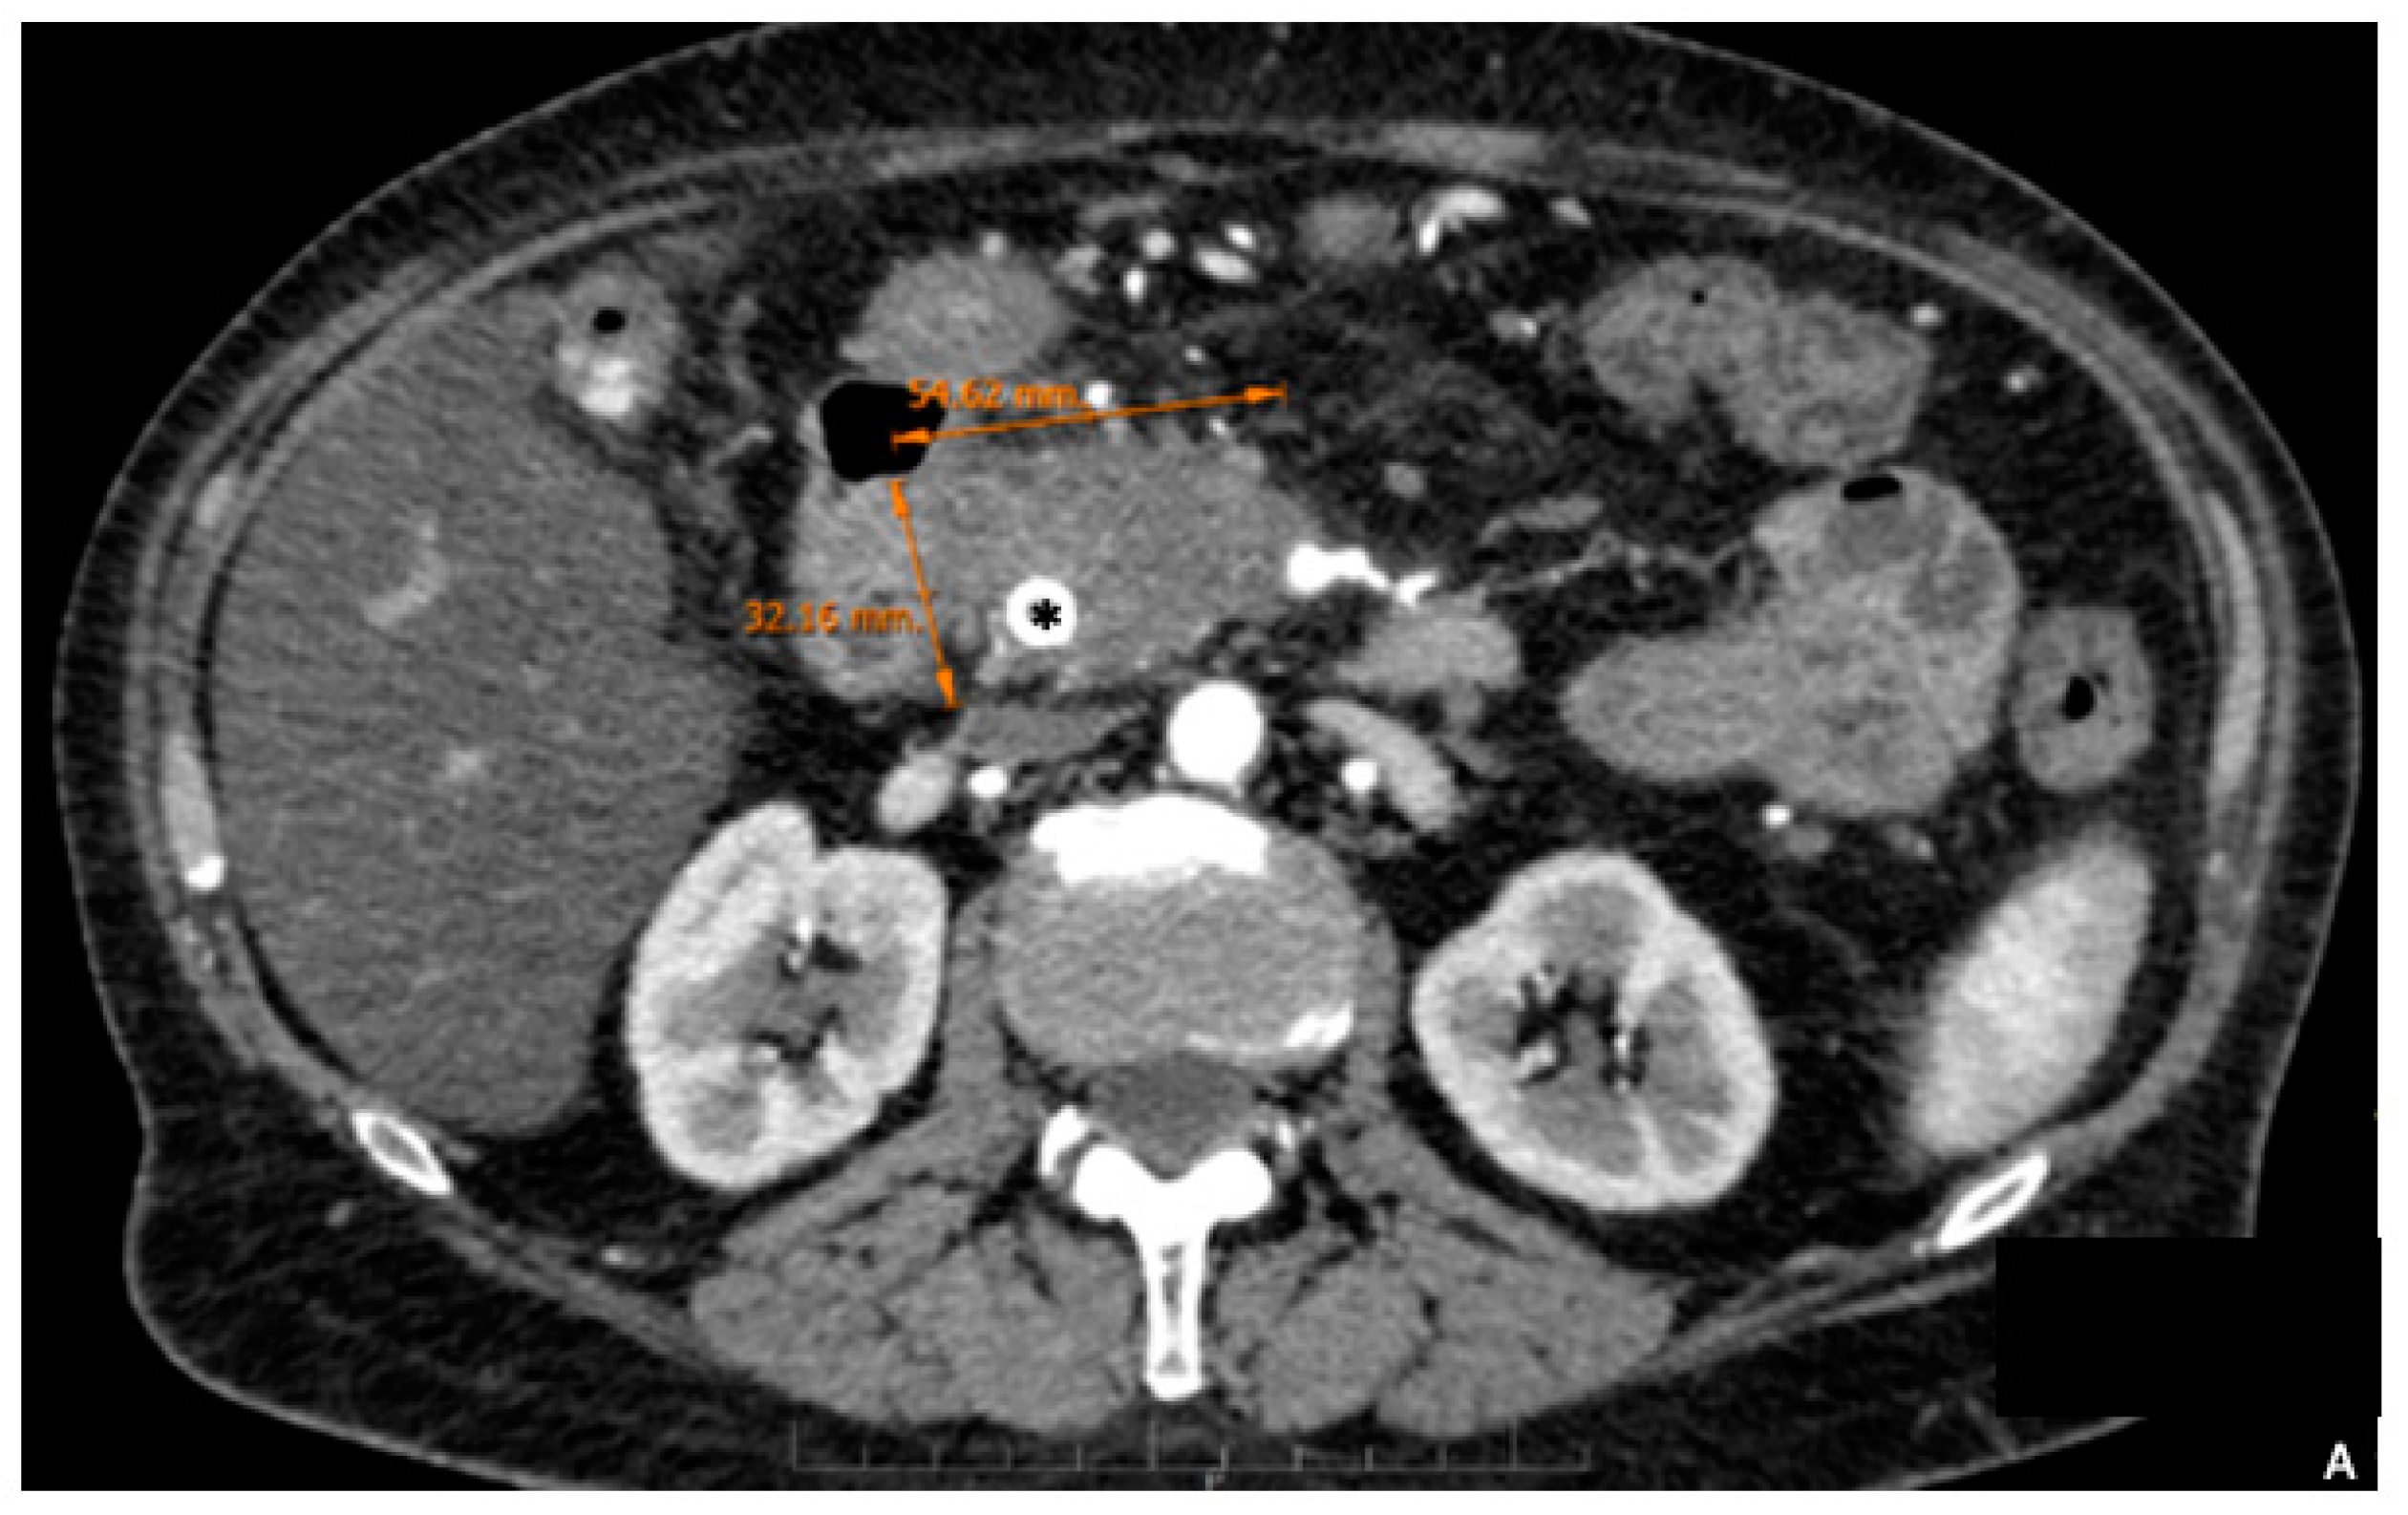

2. Preoperative Surgical Planning